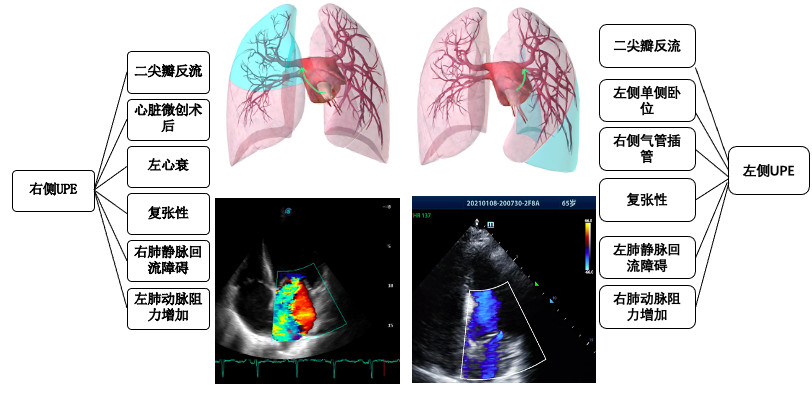

单侧毛细血管静水压明显升高。如缺血、创伤、穿孔等导致二尖瓣反流使得单侧或单支肺静脉压明显升高等[26-30](见图 1)。单侧或单支肺静脉受压、狭窄、堵塞、解剖变异、手术缝合、血栓形成、左心房肿物、硬化性纵膈炎等回流受阻导致同侧PE[31-36];一侧肺动脉阻力增加,如动脉瘤、主动脉夹层、扩大的左心室等压迫肺动脉[37, 33, 38],急性单侧肺栓塞、单侧大量气胸导致对侧血流快速增加诱发对侧PE[24, 39];支气管单侧堵塞发生患侧血管缺氧收缩诱发对侧UPE[40];长时间单侧卧位[41]。总之导致单肺血流增加的因素都可能诱发UPE。

| 图 1 UPE病因 |

UPE可根据诱因分为心源性UPE和非心源性UPE,心源性UPE主要由二尖瓣反流和左心衰导致,主要累及右侧(见图 1);而非心源性UPE诱因众多(见表 1)。